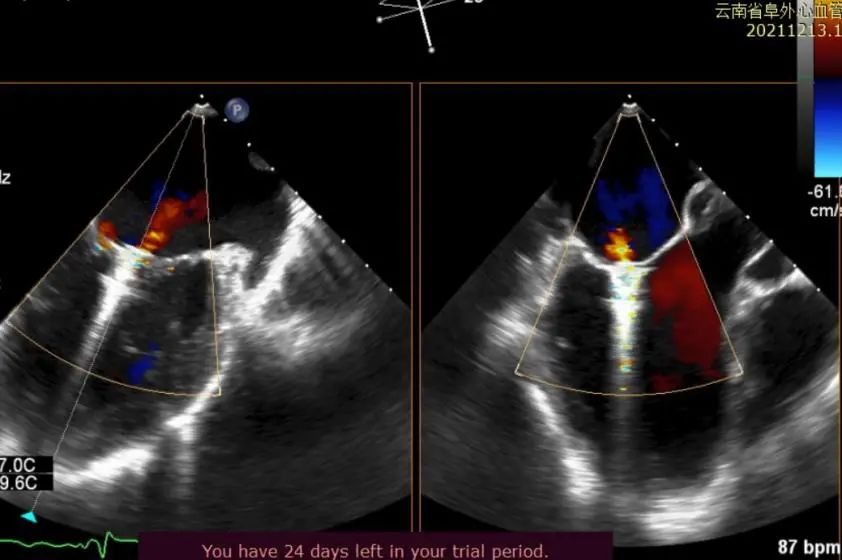

图1:患者术前TEE Biplane提示重度二尖瓣功能性反流

图2:术前3D Color TEE提示重度功能性二尖瓣反流